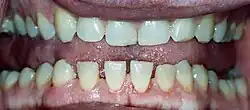

Lower jaw showing the classic spacing of teeth due to acromegaly.

Mandibular overgrowth leads to prognathism, maxillary widening, teeth spacing and malocclusion